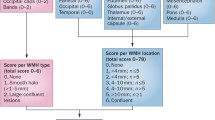

Cerebral microbleeds (CMBs) are characterized as small (<5 mm) hypointense foci that are detected on T2*-weighted gradient-recalled echo (GRE) MRI sequences [28]. The hypointense signal on the GRE sequence represents hemosiderin, a product of red blood cell hemolysis, which is cloistered indefinitely by perivascular macrophages [29]. In an update of the Rotterdam Scan study, Poels et al reported that the prevalence of CMBs increases with age. In the cohort of 3979 subjects, the prevalence of CMBs was 35.7 % in subjects 80 years of age and older, whereas the prevalence was 6.5 % in subjects 45 to 50 years of age [30]. Similar to previous findings, risk factors associated with CMBs differed based on location. Subcortical CMBs are associated with classic cardiovascular risk factors such as uncontrolled hypertension and smoking, but lobar CMBs are associated with cerebral amyloid angiopathy (CAA) [15, 30, 31]. A small 5-year cohort follow-up of 21 subjects with ischemic stroke or transient ischemic attack showed that the greatest predictors of new CMB formation were baseline CMBs (OR 1.2; 95 % CI, 1.02–141.34; P = 0.048) and mean systolic blood pressure (OR 1.28 per unit increase; 95 % CI, 1.23–1.33; P < 0.001) [32]. A study of 742 healthy subjects without classic cardiovascular risk factors suggests a high prevalence of hippocampal atrophy in subjects with CMBs vs. subjects without CMBs (P < 0.0005); however, the number of subjects with CMBs in this study was small (n = 17) [33].

CBMs are associated with VCI, and appear to effect specific cognitive domains [34, 35]. In elderly patients with moderate to severe CAA, there was an association with impaired perceptual speed and episodic memory, but spared semantic and working memory [34]. A small longitudinal cohort of stroke patients showed an association of CMBs with frontal executive dysfunction after a median follow-up of 5.7 years [35]. Interestingly, Tang et al found that an absence of CMBs was an independent factor for reversion from cognitive impairment, no dementia to normal cognition at 15-month follow-up after an acute ischemic stroke (OR 4.3, P = 0.027) [36].

The location of the CMBs play a role in the type of cognitive domains effected, although there is some inconsistency among the various studies even after adjustment for other vascular risk factors [37, 38]. These incongruences mostly appear related to the differences between study population demographics and sample sizes. The Radbound University Nijmegen Diffusion Tensor and Magnetic Resonance Cohort (RUN DMC) study of 500 subjects without dementia showed that CMBs located in the frontal and temporal lobes as well as isolated subcortical CMBs were correlated with impaired cognitive function as measured by the Mini Mental State Examination (MMSE) and Cognitive Index [37]. A substudy of 439 subjects in the Prospective Study of Pravastatin in the Elderly at Risk (PROSPER), showed that CMBs with an infratentorial location were associated with impaired cognitive function specifically for memory as measured by the Immediate Picture-Word Learning test and Delayed Picture-Word Learning test, and activities of daily living as measured by the Instrumental Activities of Daily Living [38].

The AGES-Reykjavik study is an evaluation of memory, executive function, and processing in 3906 older subjects with CMBs and retinal microvascular damage. Multiple CMBs located in the subcortex or infratentorial region were associated with lower cognitive scores on all of the tested batteries, and multiple CMBs were also associated with increased odds ratio of vascular dementia although this was not location specific (OR 2.32, 95 % CI 1.02–5.25). A finding of both multiple CMBs and retinopathy were correlated with impaired executive function and processing speed, but not memory. There was also increased odds ratio of vascular dementia with concurrent retinopathy and multiple CMBs with a lobar location (OR 3.11, 95 % CI 1.11–8.62) [39]. The Rotterdam Scan study is another large study evaluating CMBs and specific cognitive domains as measured by the MMSE and neuropsychological batteries in 3979 subjects without dementia. The presence of 5 or more microbleeds was correlated with impaired cognitive function except for memory when located in purely lobar regions. Cognitive impairment was not seen for deep or infratentorial CMBs after adjusting for other risk factors [40]. An ongoing study that may further clarify some discrepancies regarding CMB location and VCI is the Lothian Birth Cohort 1936. The 1901 healthy subjects underwent intelligence testing at age 11 and are currently undergoing extensive testing which includes cognitive batteries and T2*GRE MRI sequences to assess CMBs after subjects reach 70 years of age [41].